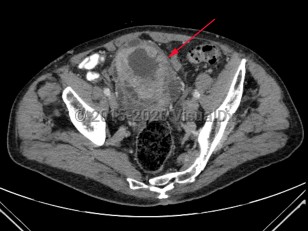

Uterine fibroidsUterine fibroids

Polycystic kidney diseasePolycystic kidney disease

EndometriosisEndometriosis